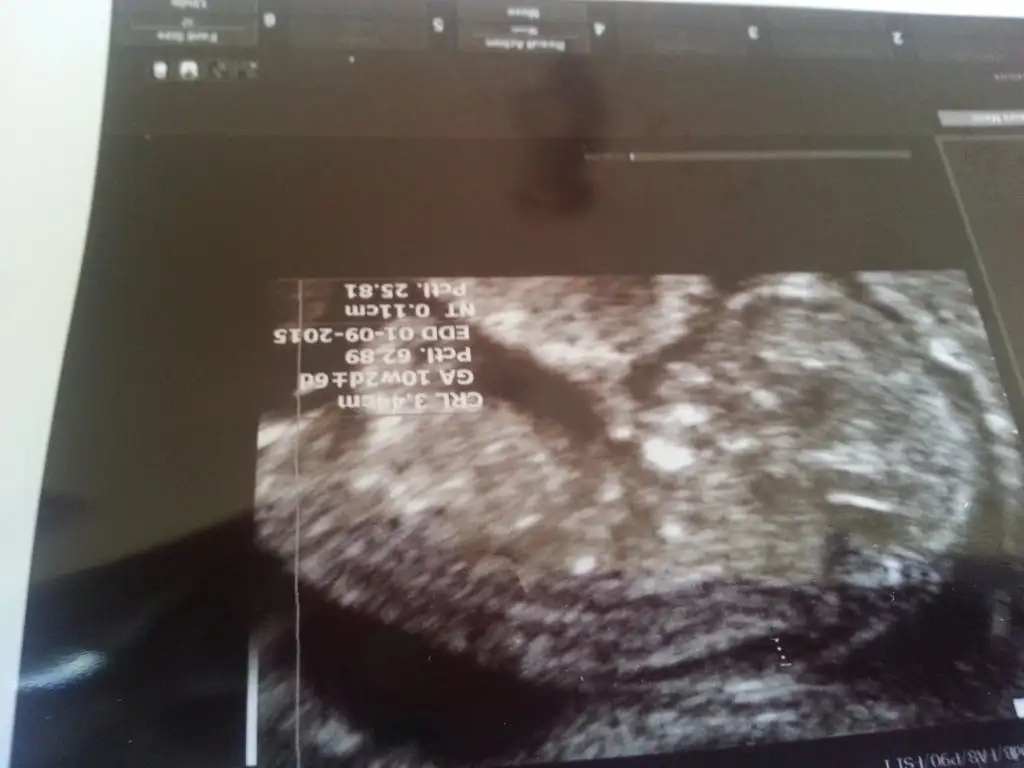

Kizlar mrb. Oncelikle hepinize saglikli mutlu bir gebelik sureci diliyorum. Benim bugun 11. Haftam bitti cok sukur. Ekte 10+2 haftalik goruntusu var bebisimin. Nub teorisine gore cinsiyeti hakkinda yorum yapabilirmisiniz? Oncelikle saglikli olmasi tabiki temennimiz. Ama merak ettim iste:)

• IMG-20150207-WA0000.webp

Bence kız canım ama sadece bi tahmin benimki kemik yapısı epey düz çünkü.

teşekkürler canım, ilk bebeğim. allah hayırlısını sağlıklısını versin tabi öncelikle. kız olsa da erkek olsa da ayrı ayrı sevinirim. ikisi de evlat sonuçta. ama ben erkeğe benzetmiştim sanki. düz kemik yapısı derken genital bölgeden bahsediyosun dimi..

evet genital bölgeden bahsediyorum ama dedigim gibi pek anlamam öyle sadece bir tahmin.. ;)